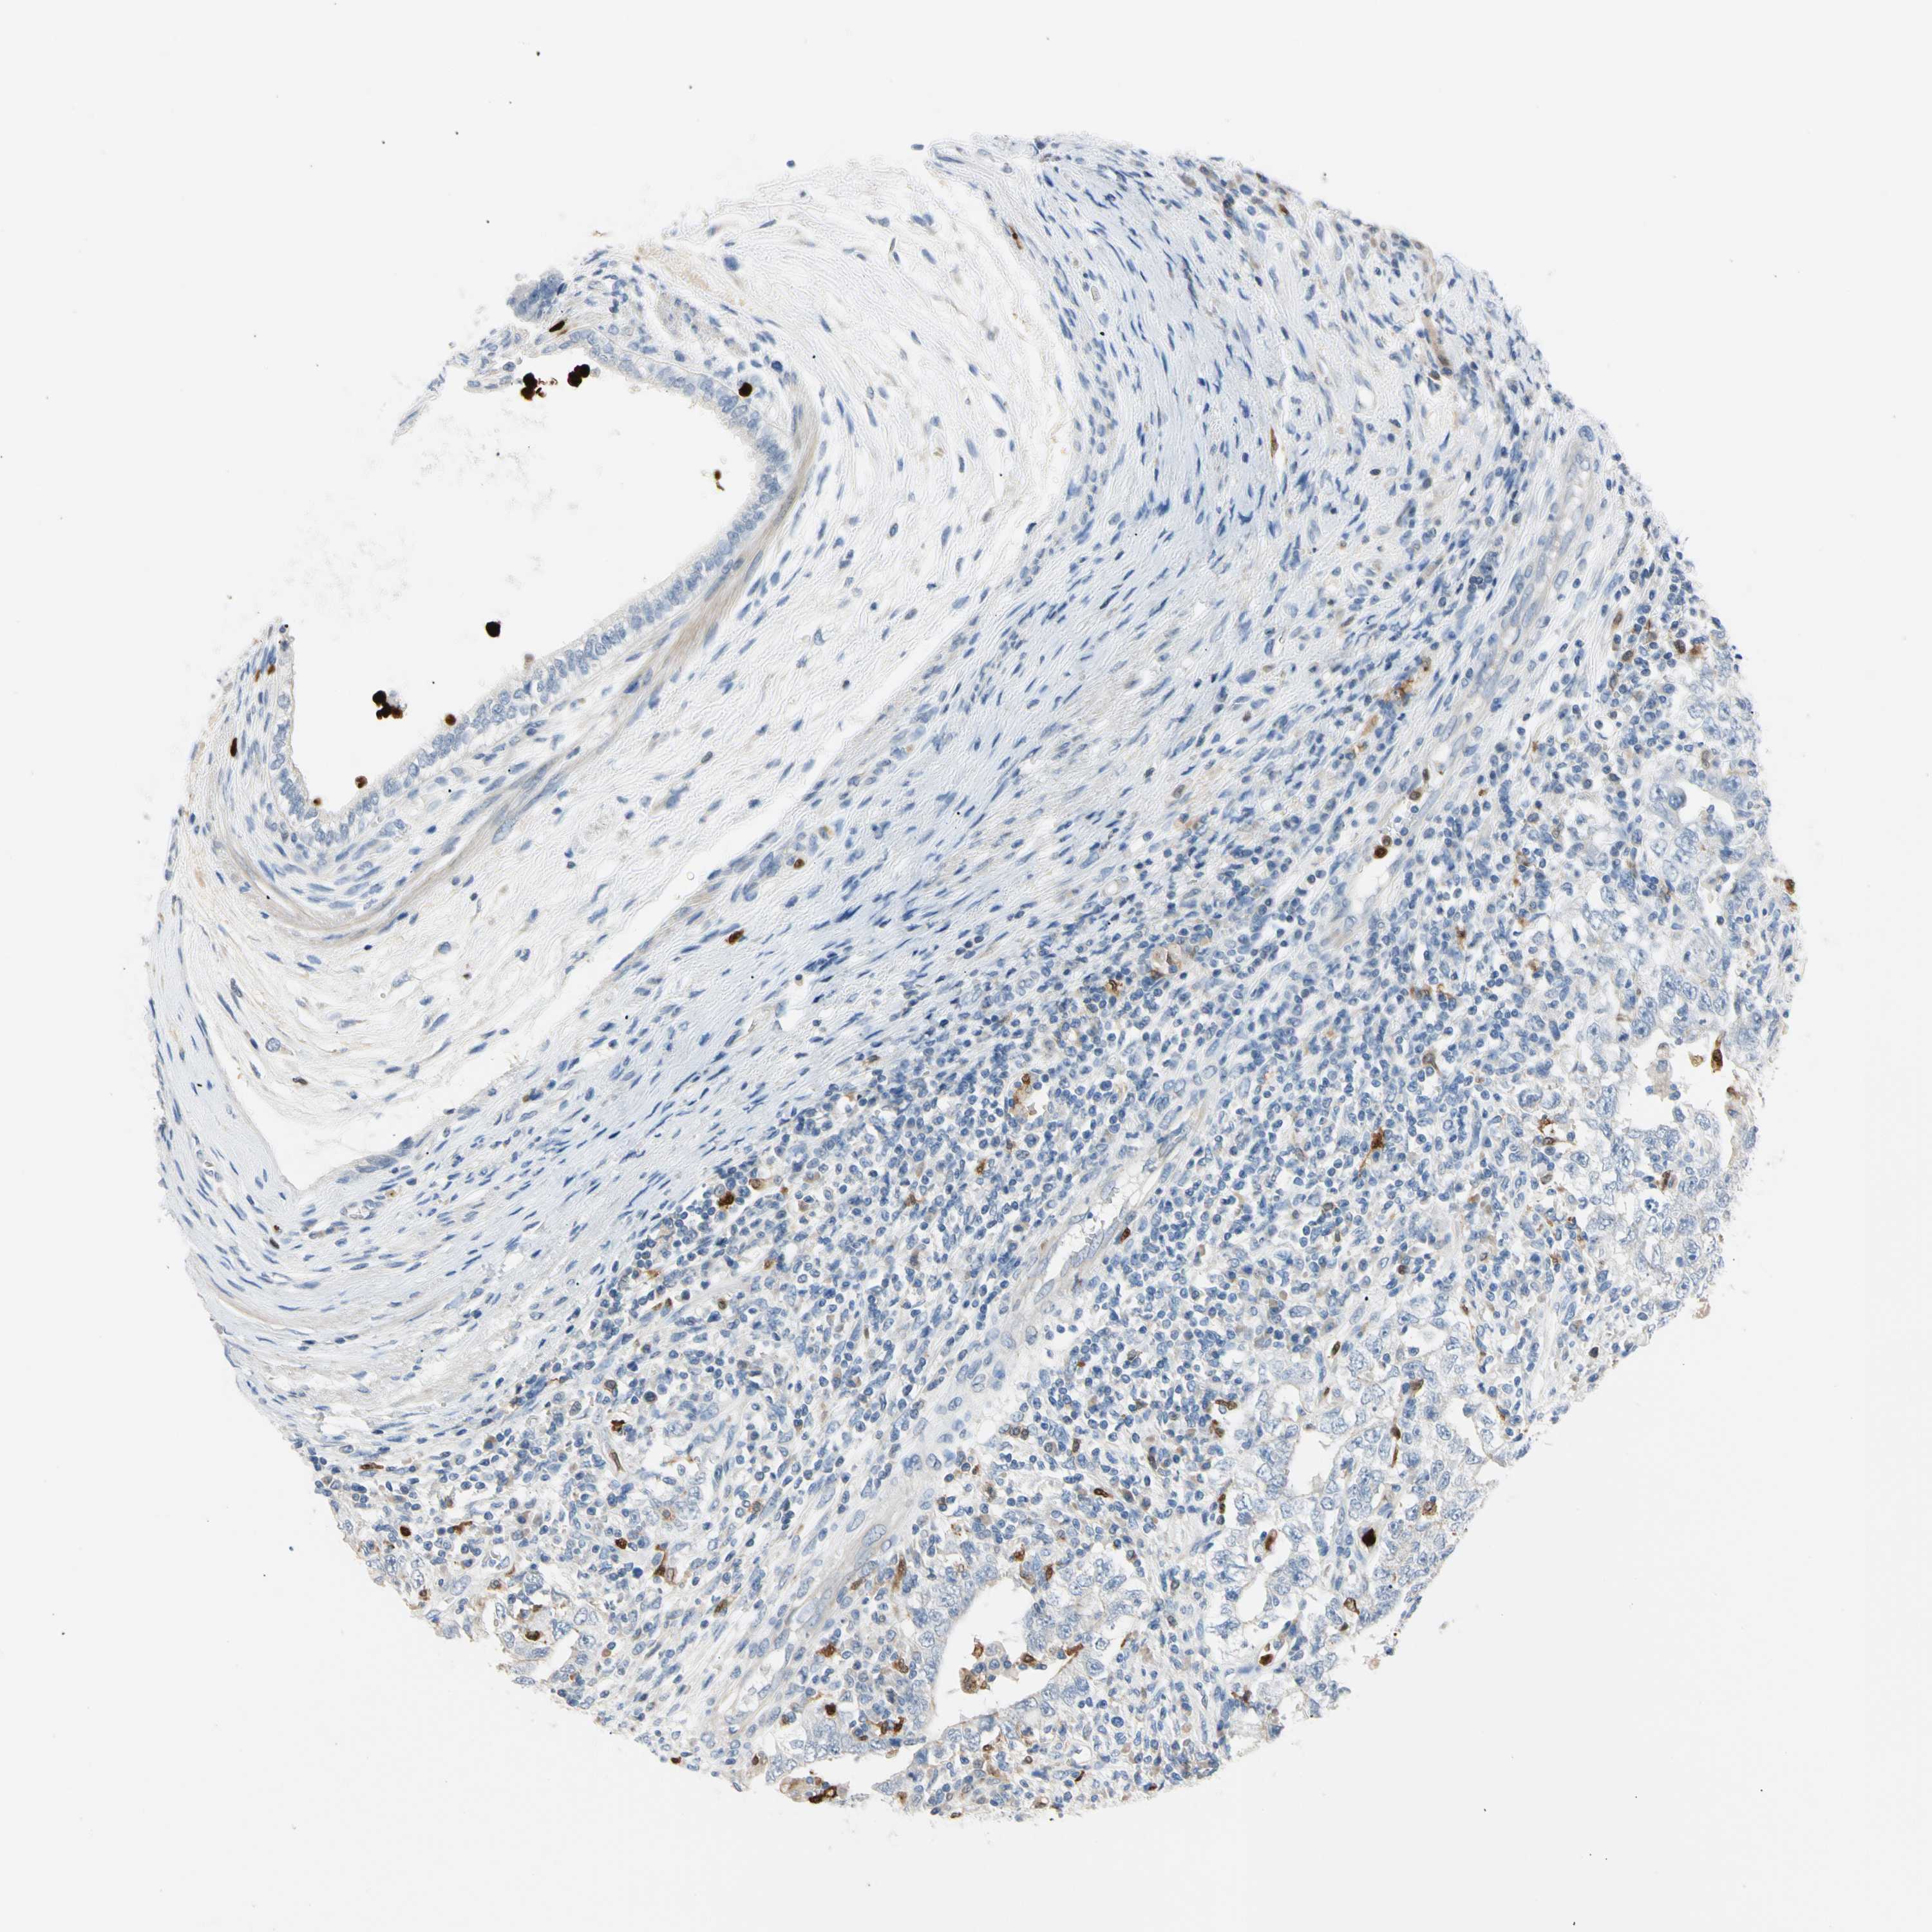

TESTIS CANCER - Protein expressioni

A mouse-over function shows sample information and annotation data. Click on an image to view it in a full screen mode. Samples can be filtered based on level of antibody staining by selecting one or several of the following categories: high, medium, low and not detected. The assay and annotation is described here.

Note that samples used for immunohistochemistry by the Human Protein Atlas do not correspond to samples in the TCGA dataset.

Antibody stainingi

Antibody staining in the annotated cell types in the current human tissue is reported as not detected, low, medium, or high, based on conventional immunohistochemistry profiling in selected tissues. This score is based on the combination of the staining intensity and fraction of stained cells.

Each image is clickable and will lead to virtual microscopy that enables deeper exploration of all samples and also displays staining intensity scores, fraction scores and subcellular localization as well as patient and tissue information for each sample.

Antibody HPA008052

Antibody CAB010277

Carcinoma, Embryonal, NOS

Seminoma, NOS